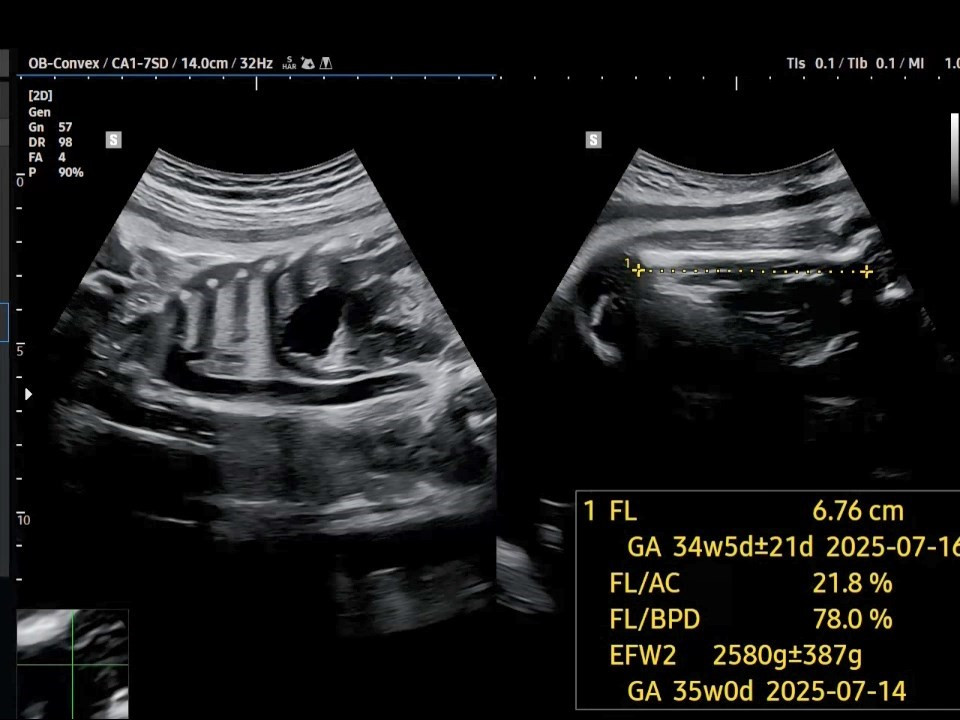

3. 허벅지 뼈의 길이(FL: Femur Length)는 6.76㎝로 나오는데, 이것도 34주 차에 해당되네요. 그리고 태아 추정 체중(EFW: Estimated Fetal Weight)은 약 2.5~2.6㎏으로 나옵니다. 이 또한 평균보다는 좀 작은 편입니다.

37주 FL.jpg [37주 차 허벅지뼈 길이]